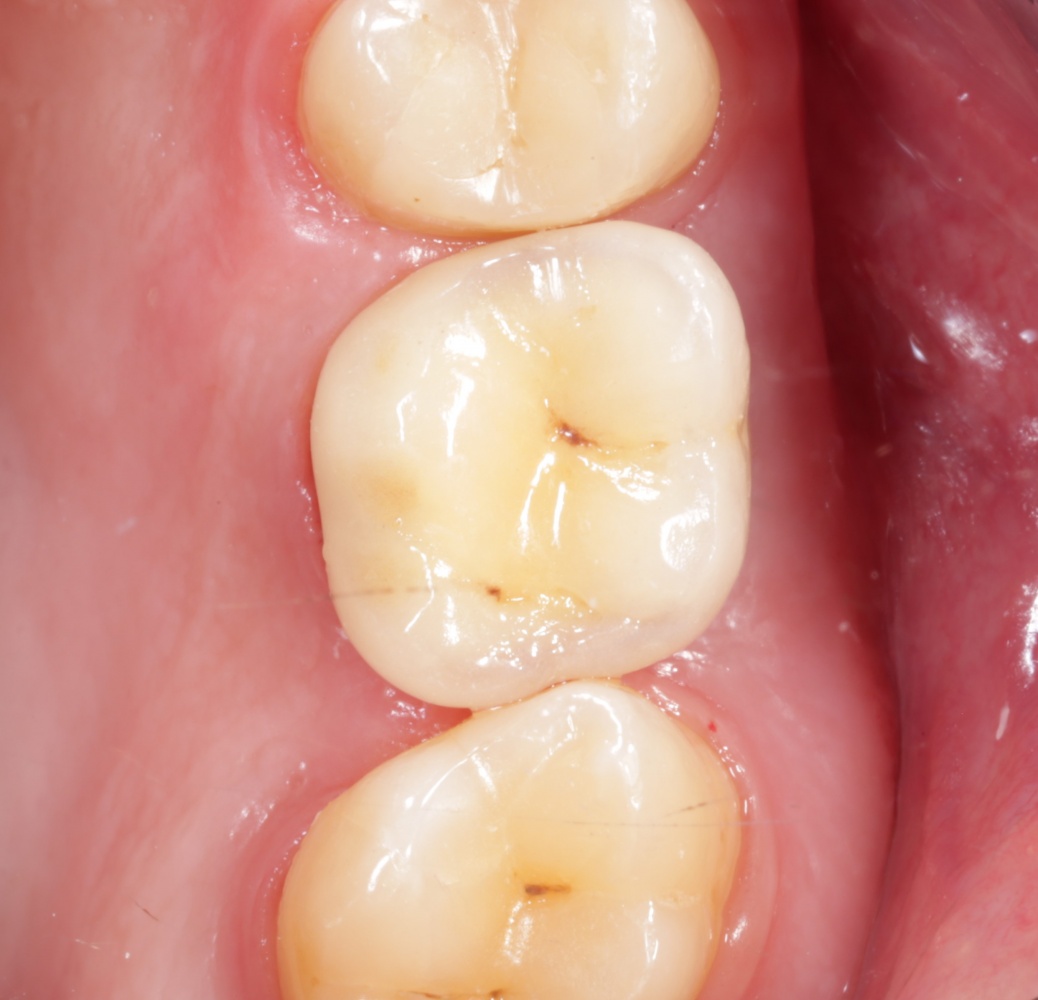

А через два месяца — вот так:

На этом этапе, для создания более правильного десневого контура, можно поменять формирователь размер больше:

А еще через месяц — поставить временную коронку:

Могли бы мы в этом случае обойтись без аугментации лунки? Вполне, могли бы. Но в этом случае окружающие коронку ткани выглядели бы иначе, а сам пациент испытывал бы проблемы с уходом — из-за утраты объемов, у него постоянно застревали бы остатки пищи между коронкой и десной.